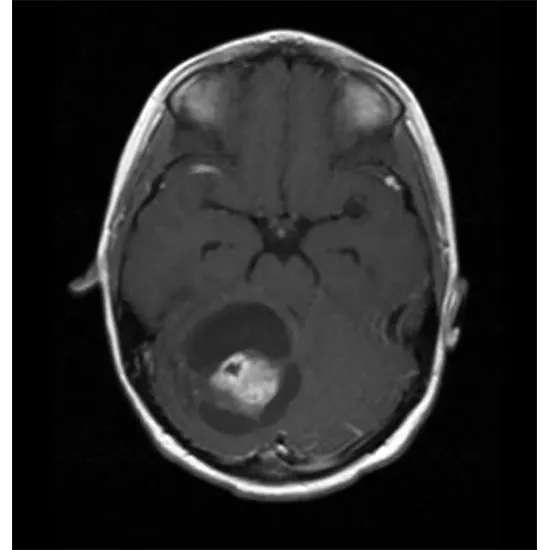

Imaging tests. Imaging tests can assist to your specialist in determining the area and size of your brain tumor. MRI is frequently used to diagnose brain tumors, and it may be used alongside specialized MRI imaging techniques, such as useful MRI, perfusion MRI, and attractive reverberation spectroscopy.

Other imaging tests may incorporate CT and positron emission tomography (PET).